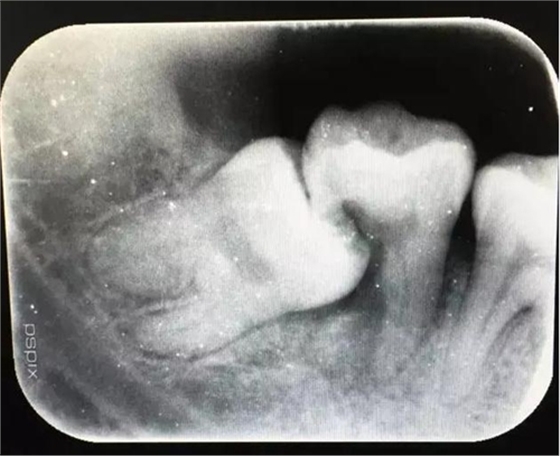

患者、申xx、女、40歲,主訴:左側(cè)下頜后牙牙齦紅腫不適數(shù)月。??茩z查:37合面有一開髓孔。髓腔內(nèi)有一暫封小棉球,探針?biāo)枨坏撞砍鲅?,疑為在外院治療?dǎo)致底穿。x線片檢查:37頰側(cè)齦下有一枚多生牙,多生牙壓迫頰側(cè)牙根及牙體組織大量吸收。

圖2.術(shù)前的x線根尖片影像檢查:47遠(yuǎn)中牙根吸收。